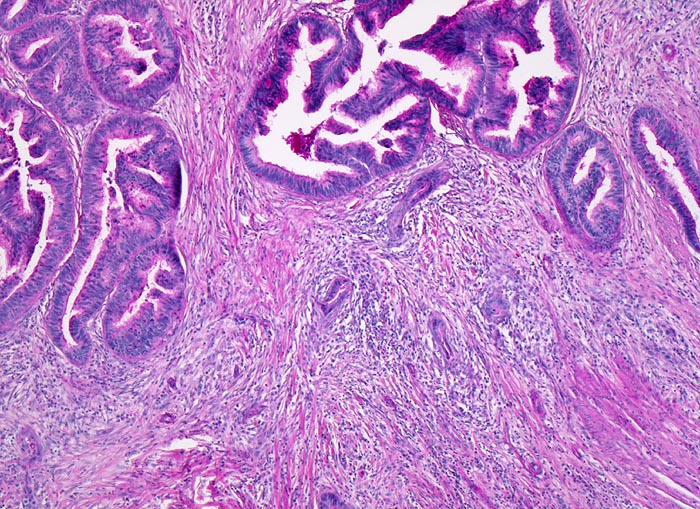

Morphologie:

Die meisten Adenokarzinome des Kolons bilden Drüsen. Die Drüsenlumina enthalten oft nekrotischen Detritus und variable Mengen von Schleim. Der intraluminale nekrotische Detritus findet sich oft auch in den Metastasen kolorektaler Karzinome und gibt einen morphologischen Hinweis auf die Lokalisation des Primärtumors, wenn nur Gewebe aus einer Metastase für die histologische Untersuchung zur Verfügung steht.

Das Tumorgrading basiert auf dem Ausmass der Drüsenbildung (>50% Drüsenbildung = low grade, <50% Drüsenbildung = high grade).

Prognostisch ungünstige histologische Parameter sind Lymphgefäss- und Veneninvasion, Perineuralscheideninvasion, hohes Tumorbudding (zahlreiche kleine Tumorzellcluster im Bereich der Tumorinvasionsfront) und Nachweis von Tumorgewebe im Resektionsrand.